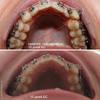

Достала фотоаппарат, сделала фото, слепила коллажик и вуаля! Вот мои первые шажочки найдите три отличия! Может кому-то они покажутся незаметными и незначительными, но для меня это радость. Вот такая - Огромная радость размером в пару миллиметров!

Есть, правда, еще одна маленькая радость и одно большое огорчение. Из радости - мой рот после сложного удаления 8-ки стал еще чуть-чуть больше открываться, чем прежде но суши и роллы в него целиком так и не пролазят... эх, а раньше влетали без остановки, как вареники в "Вечера(х) на хуторе близ Диканьки". Поэтому я смогла наконец сделать фото ВЧ снизу. Но, к сожалению, сравнить не с чем, так как в первый день ношения БС я так рот открыть еще не могла и фото, соответственно, нет. Но вот и огорчение. Вчера, когда рассматривать низ ВЧ между клыком и злополучной четверкой я обнаружила щербинку прям на стенках слияния этих двух зубов у самой десны. Что это может быть? скорее всего кариес... А кариес может быть НЕ черной дырочкой? у меня там нет черноты, но есть вот эта щербинка..., но это не образовавшаяся щель, это именно дырочка в стенке зуба. Короче, конкретная у меня печалька